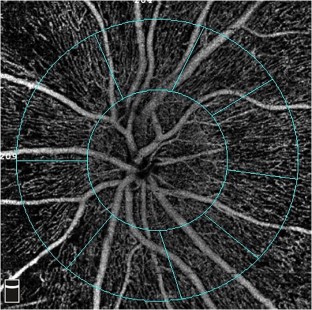

The study was designed as a prospective observational study. Twenty-four eyes were included. Eyes with retinal vascular pathology, any type of age-related macular degeneration, IOP more than 21 mmHg, axial length less than 20 mm and more than 24 mm, corneal edema and cataracts that can disrupt images, and history of ocular surgery were excluded. Patients underwent OCTA imaging and IOP measurement preoperatively (baseline) and postoperatively (weeks 1 and 4). Vessel density % (VD) in the total disc, peripapillary, and inside disc were measured. IOP was measured with the applanation tonometer. Comparison of VD and IOP and correlation between VD and İOP change were determined.

VD was significantly increased in all quadrants in week 4 compared to those in week 1. In terms of VD and IOP, although there was no significant difference between week 1 and baseline, week 4 results were significantly different from baseline (p < 0.05 and p < 0.001, respectively). The IOP was significantly lower in week 4 (14.8 mmHg) than in week 1 (16.0 mmHg) (p < 0.001). There was a significant negative correlation between the inside disc and total VD and IOP at weeks 1 and 4.

Phacoemulsification surgery can result in a decrease in IOP and an increase in VD of the ONH.